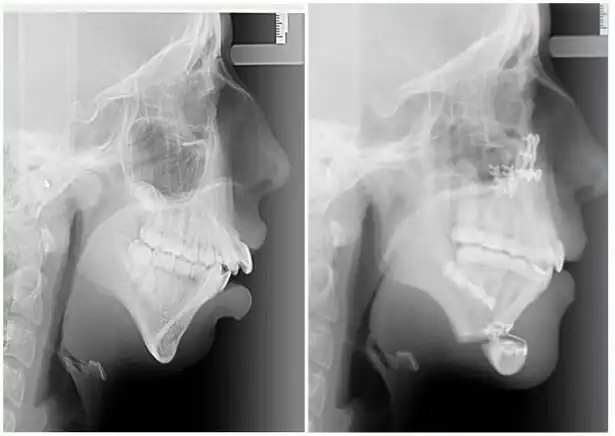

Девушка по имени Элли Джонс (Ellie Jones) родилась с врожденным состоянием лица, которое отразилось на том, что в возрасте 8 лет челюсть Элли просто перестала расти. В результате этого кости нижней части лица девушки перестали развиваться должным образом и были меньше нормального размера. Этот недуг был обнаружен ортодонтом, который сразу догадался в чём проблема, как только девушка пришла к нему на установку скобок в 14 лет.

Первую операцию по преобразованию челюсти Элли перенесла в 16 лет.

Операция заключалась в вырезании челюсти по горизонтали и вертикали с последующим ещё большим хирургическим вмешательством.